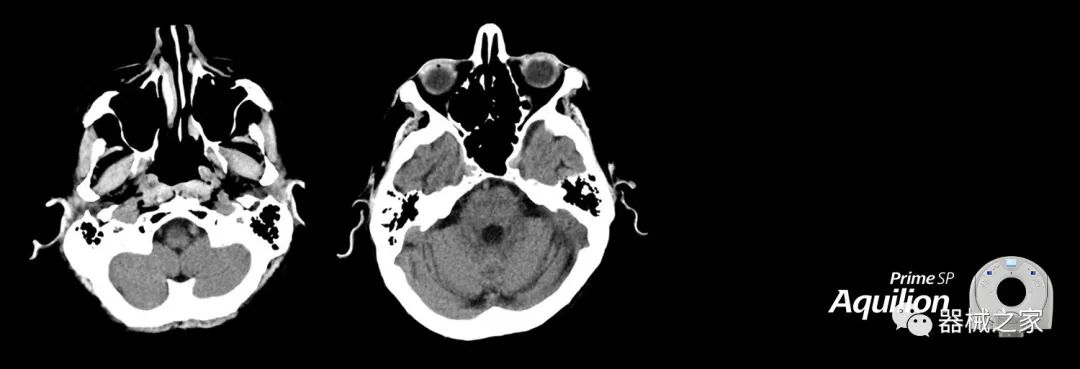

在以患者為中心的放射腫瘤學(xué)領(lǐng)域,計(jì)算機(jī)斷層掃描(CT)的可訪問性,可重復(fù)性和靈活性至關(guān)重要。為了建立這些價(jià)值,佳能醫(yī)療系統(tǒng)美國公司現(xiàn)在正在擴(kuò)大其放射腫瘤學(xué)CT模擬產(chǎn)品,包括Aquilion Prime SP和Aquilion Lightning 80高級(jí)CT系統(tǒng)。除了Aquilion LB之外,Aquilion Prime SP和Aquilion Lightning 80現(xiàn)在還包括放射治療(RT)選項(xiàng),可為腫瘤學(xué)規(guī)劃提供高質(zhì)量的CT成像和精密工具。

Aquilion Prime SP使設(shè)施能夠處理具有挑戰(zhàn)性的案例,同時(shí)為員工提供快速,靈活和高效的解決方案。

兩個(gè)CT系統(tǒng)均采用0.5 mm x 80排PUREViSION探測(cè)器技術(shù)(可配置并從80-160現(xiàn)場(chǎng)升級(jí)),78 cm孔徑,50 cm視野,AIDR(自適應(yīng)迭代劑量減少)3-D和SEMAR(單個(gè))能量金屬神器減少)技術(shù)。